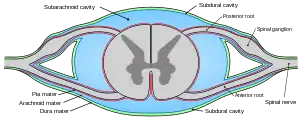

Diagrammatic representation of a section across the top of the skull, showing the membranes of the brain, etc. Diagrammatic transverse section of the medulla spinalis and its membranes

Diagrammatic transverse section of the medulla spinalis and its membranes- Spinal cord. Spinal membranes and nerve roots. Deep dissection. Posterior view.